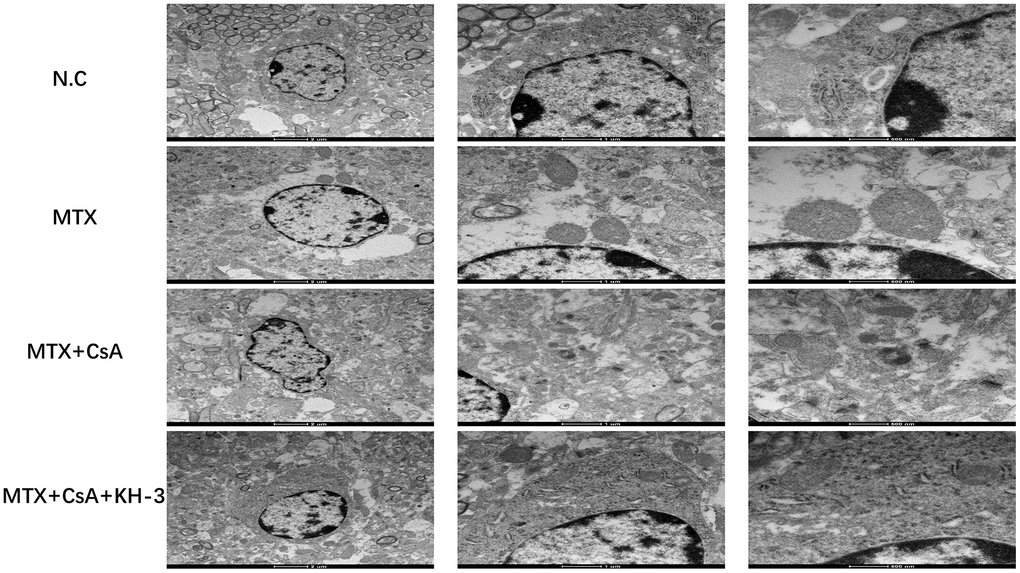

Ultrastructural mitochondrial changes in the hippocampus in different groups

As shown in Figure 4, which displays transmission electron microscopy results, MTX caused damages to the mitochondrial structure, such as mitochondrial swelling and dark mitochondrial matrix, in hippocampal tissues. Compared to the control group, the number of autophagosomes in the MTX group appeared to decrease, although statistical analysis was not possible. After CsA intervention, the morphology of mitochondria seemed to improve. However, the protective impact of CsA over mitochondria was halted by KH-3, including shrinkage of the mitochondrial membrane and a reduction in or the disappearance of mitochondrial cristae.